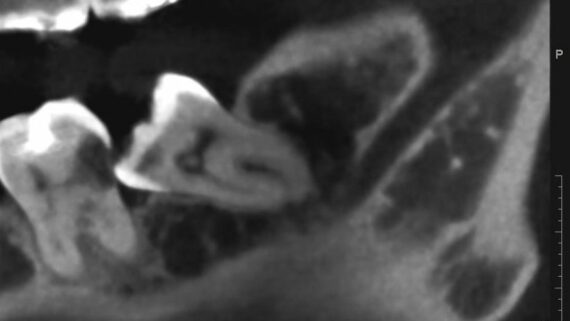

Итак, вот изначальная ситуация:

И вот ситуация конечная, уже с имплантами. С начала лечения прошло три месяца.

Я понимаю, что данных на части панорамного снимка очень мало для правильной интерпретации клинической ситуации, но, с другой стороны, это позволит не перегрузить Вас информацией.

- боковой сегмент, отсутствуют три зуба: 35, 36, 37. Эти зубы удалены достаточно давно, развилась сильная атрофия костной ткани.

- верхние зубы, не имея антагонистов, выдвинулись вниз (зубоальвеолярное удлинение, т. н. «симптом Попова-Годона»).

Их несколько, они обозначены на снимке.

- Значительная атрофия костной ткани, особенно по высоте. Решается: остеопластической операцией.

- Зубоальвеолярное удлинение в области зубов-антагонистов. Решается: ортодонтическим лечением.

Вот снимок после операции:

И с обозначениями:

«Пустое пространство» под блоком мы заполнили аутокостной стружкой, а сверху закрыли барьерной мембраной BioGide. Самое сложное в данной работе было, на мой взгляд, подогнать размер блока, «собрать» слизистую оболочку и наложить швы так, чтобы пациентка не кусала послеоперационную рану верхними зубами. Кстати, как видите, на верхние зубы уже наклеили брекеты — начали ортодонтическое лечение.

Это можно увидеть по прицельному снимку, который мы сделали через 3 месяца после остеопластики:

Вспомните, как стояли винты сразу после операции и как они выглядят сейчас.

Обратите внимание на появление новообразованной костной ткани под блоком — на снимке наглядно прослеживается ее губчатая структура. Пока границы слоев костной ткани видны хорошо, но, в дальнейшем, они почти исчезнут.

Снимок после проведенной имплантации:

Винты, фиксировавшие блок, удалены. Имплантаты позиционированы по разметке ортопеда, исходя из планируемой ортопедической конструкции.

Многих пациентов также интересует, как заживает тот участок челюсти, с которого был взят костный блок для пересадки. На снимке выше очень хорошо видно, что через три месяца костная ткань там почти полностью восстановилась — область забора блока еле видна.